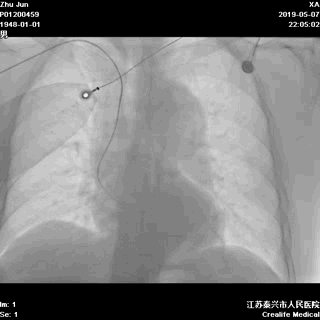

去导管室途中,全程监护,心脏除颤器伴行

胸部X-线透视,掌握患者更多基础信息